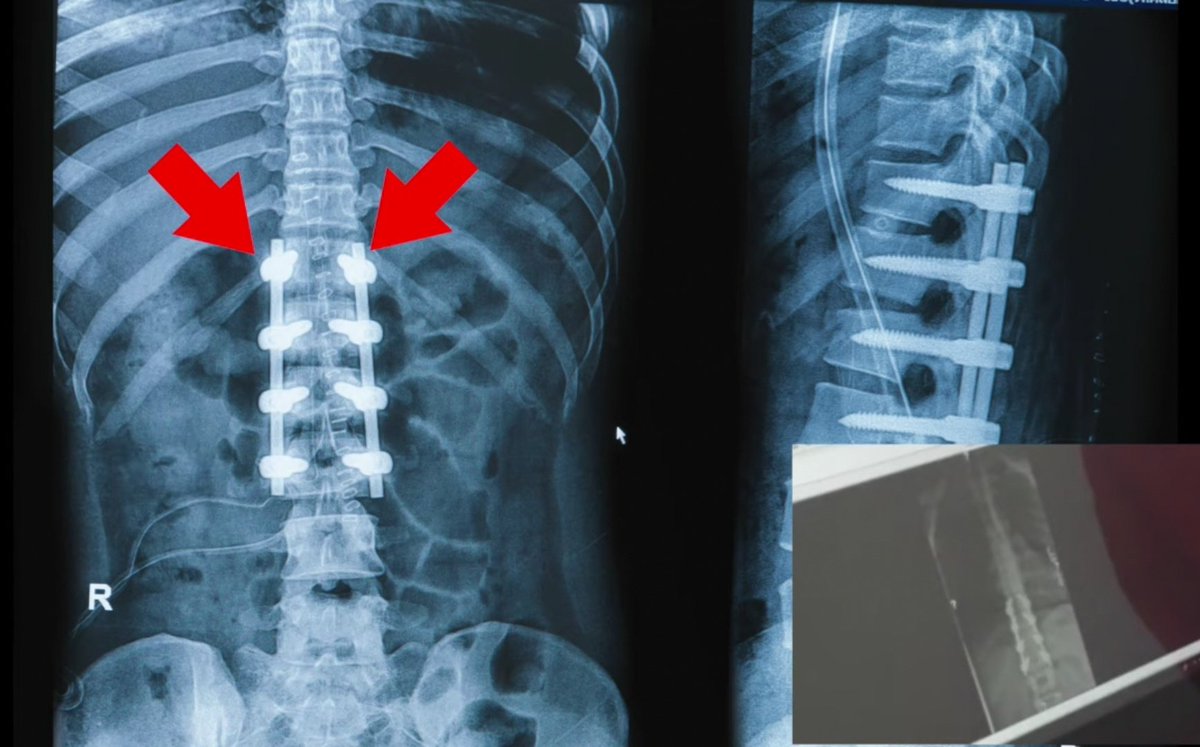

كان عبارة عن دمج 3 كسور في العمود الفقري كما هو موضح

ـ بالـ MRI?

⁦⤵️⁩